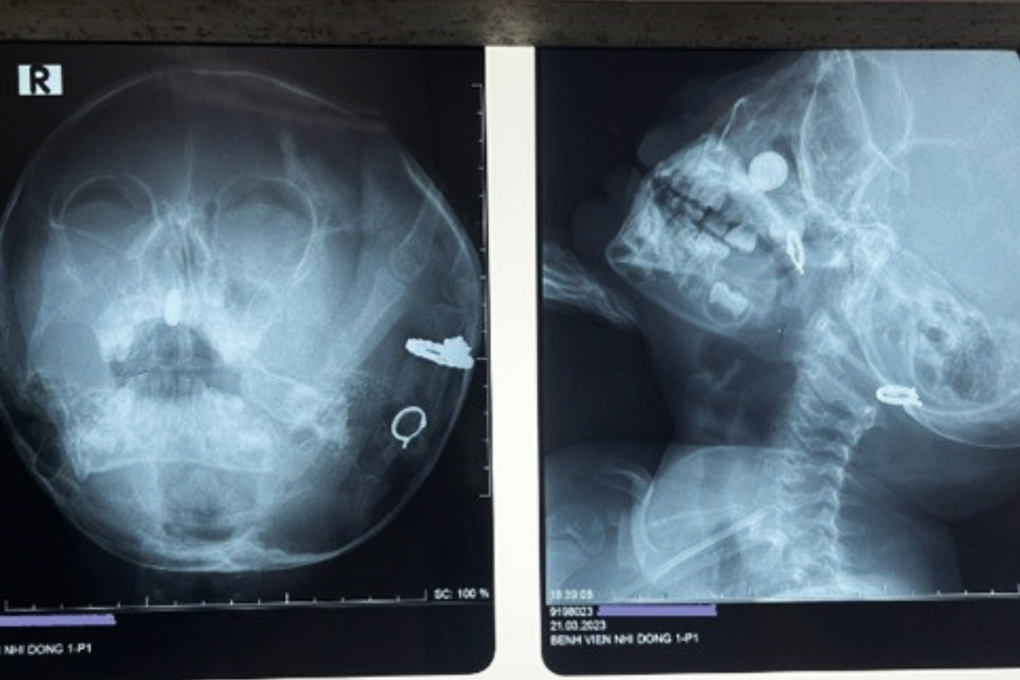

Phim chụp X-quang cho thấy dị vật trong mũi cháu bé (Ảnh: BV).

Qua thăm khám, chỉ định chụp X-quang, bác sĩ trực nhanh chóng xác định bé có dị vật trong mũi, nghi ngờ là pin điện tử dạng cúc áo. Đây là một dị vật nguy hiểm, cần nhanh chóng lấy ra ngay, vì nguy cơ pin điện tử gây thủng vách ngăn, ăn mòn các cấu trúc quan trọng từ hốc mũi. Nếu xử trí không phù hợp, vật cũng có thể trôi xuống đường thở hoặc đường ăn của bệnh nhi.